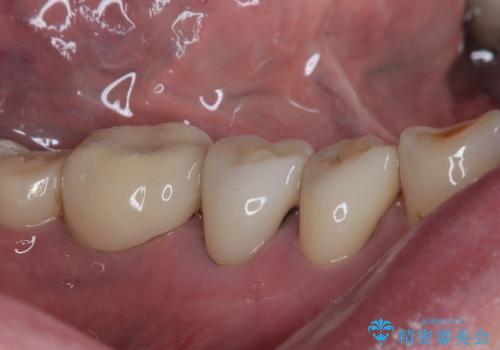

- 食事中に歯が欠けてしまったとのことで来院された患者様です。

以前詰めた材料が外れたか、歯が欠けたのかは分かりませんが、欠損している状態でした。

再度詰め物での処置を行うと引き続き欠けるリスクが高いため、高強度のフルジルコニアクラウンにて補綴治療を行うこととしました。